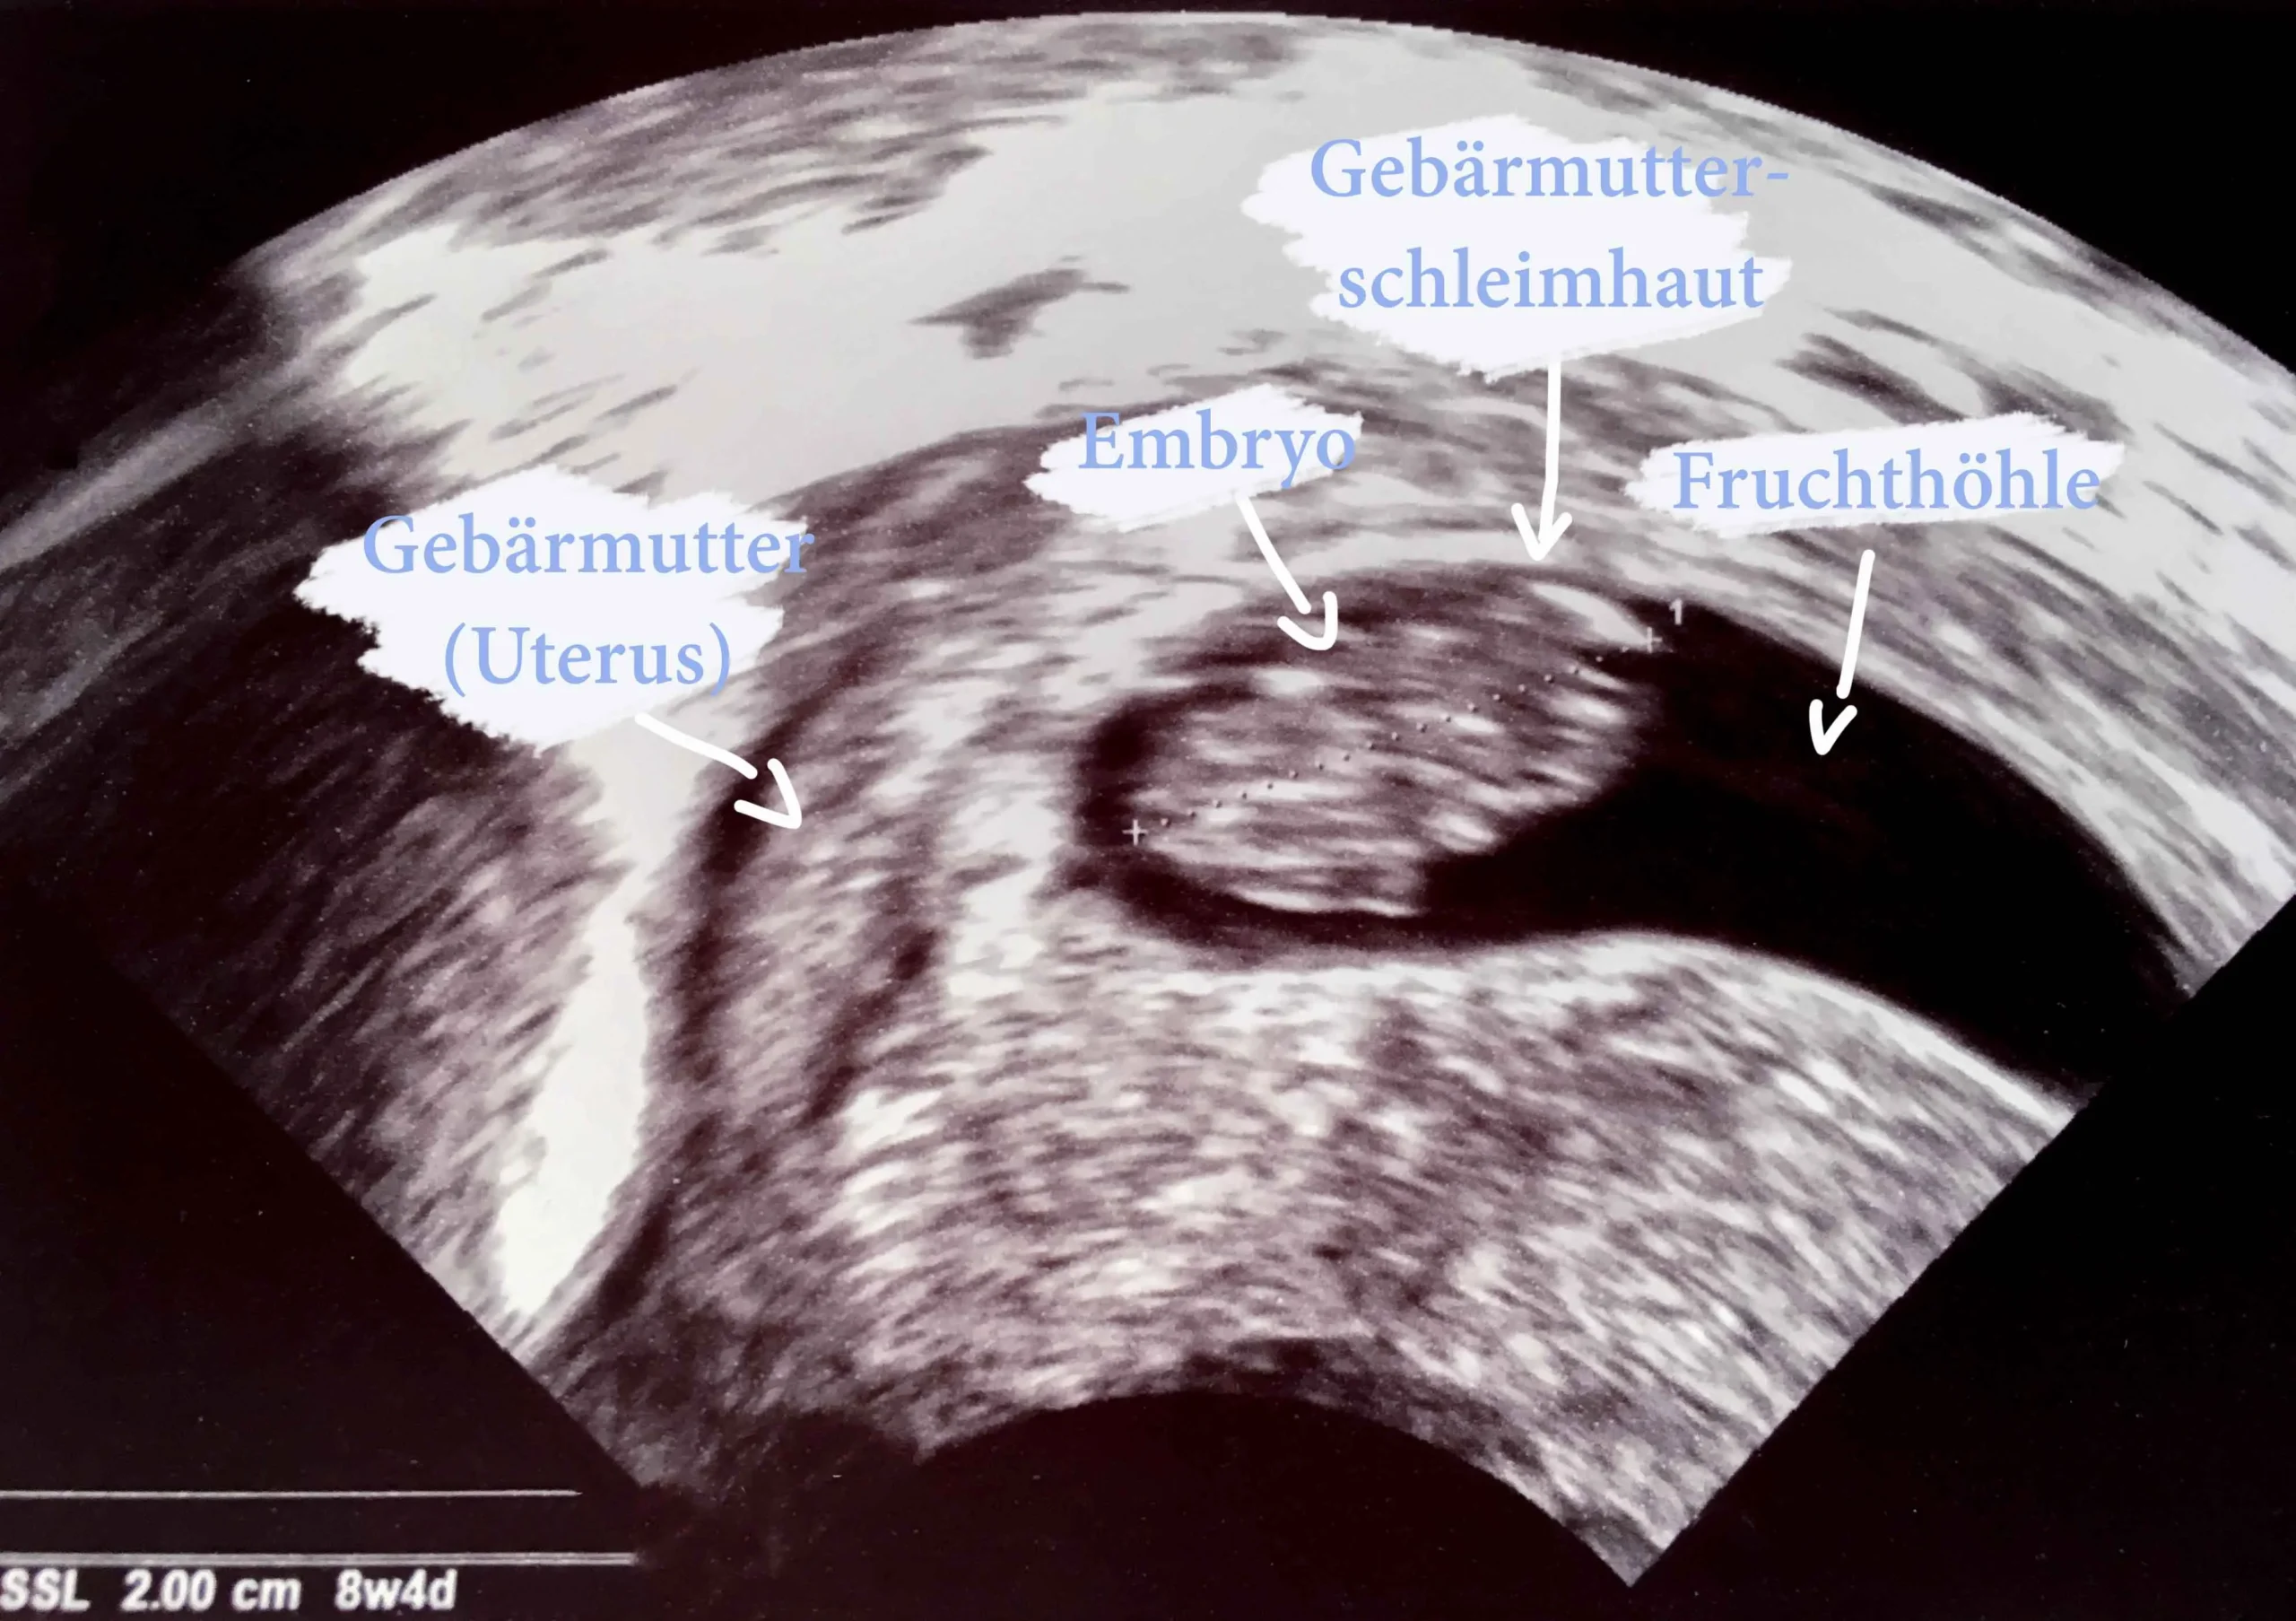

Ein Ultraschall ist eine bildgebende Technik, die Schallwellen verwendet, um Bilder von den Organen und Geweben im Körper zu erstellen. In der Schwangerschaft wird der Ultraschall verwendet, um die Entwicklung des Babys im Mutterleib zu beobachten. Der Ultraschall ist ein sicheres und schmerzloses Verfahren, das keine schädlichen Strahlen verwendet.

Die Schallwellen werden von einem kleinen Gerät, dem Schallkopf, ausgesendet, der auf den Bauch der Schwangeren gelegt wird. Die Schallwellen werden von den Organen und Geweben im Körper reflektiert und erzeugen ein Bild auf dem Bildschirm des Ultraschallgeräts.

- 2D-Ultraschall: Der 2D-Ultraschall ist die häufigste Art von Ultraschalluntersuchung. Er zeigt das Baby in Schwarzweiß auf dem Bildschirm.